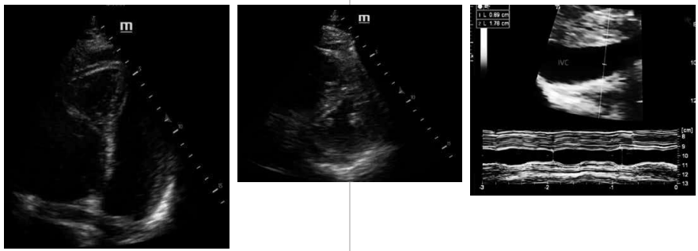

Mulher, 24 anos de idade, sem antecedentes conhecidos, deu entrada no serviço de emergência com dispneia súbita, dessaturação e taquicardia, além disso se queixava de perda de visão do lado esquerdo de ambos os olhos. Ela foi colocada na maca da emergência e monitorizada. Sinais vitais: temperatura 37,3 °C, Fc 137 bpm, sat. 92%, Fr 35 irpm, em uso de máscara não reinalante a 12 litros por minuto. Glicemia capilar: 145. Pressão arterial 97 x 85 mmHg.

Considerem-se as imagens a seguir.

Ainda com base na situação hipotética apresentada, as imagens indicam a realização de POCUS em uma paciente. Com base nessas imagens, assinale a alternativa correta.